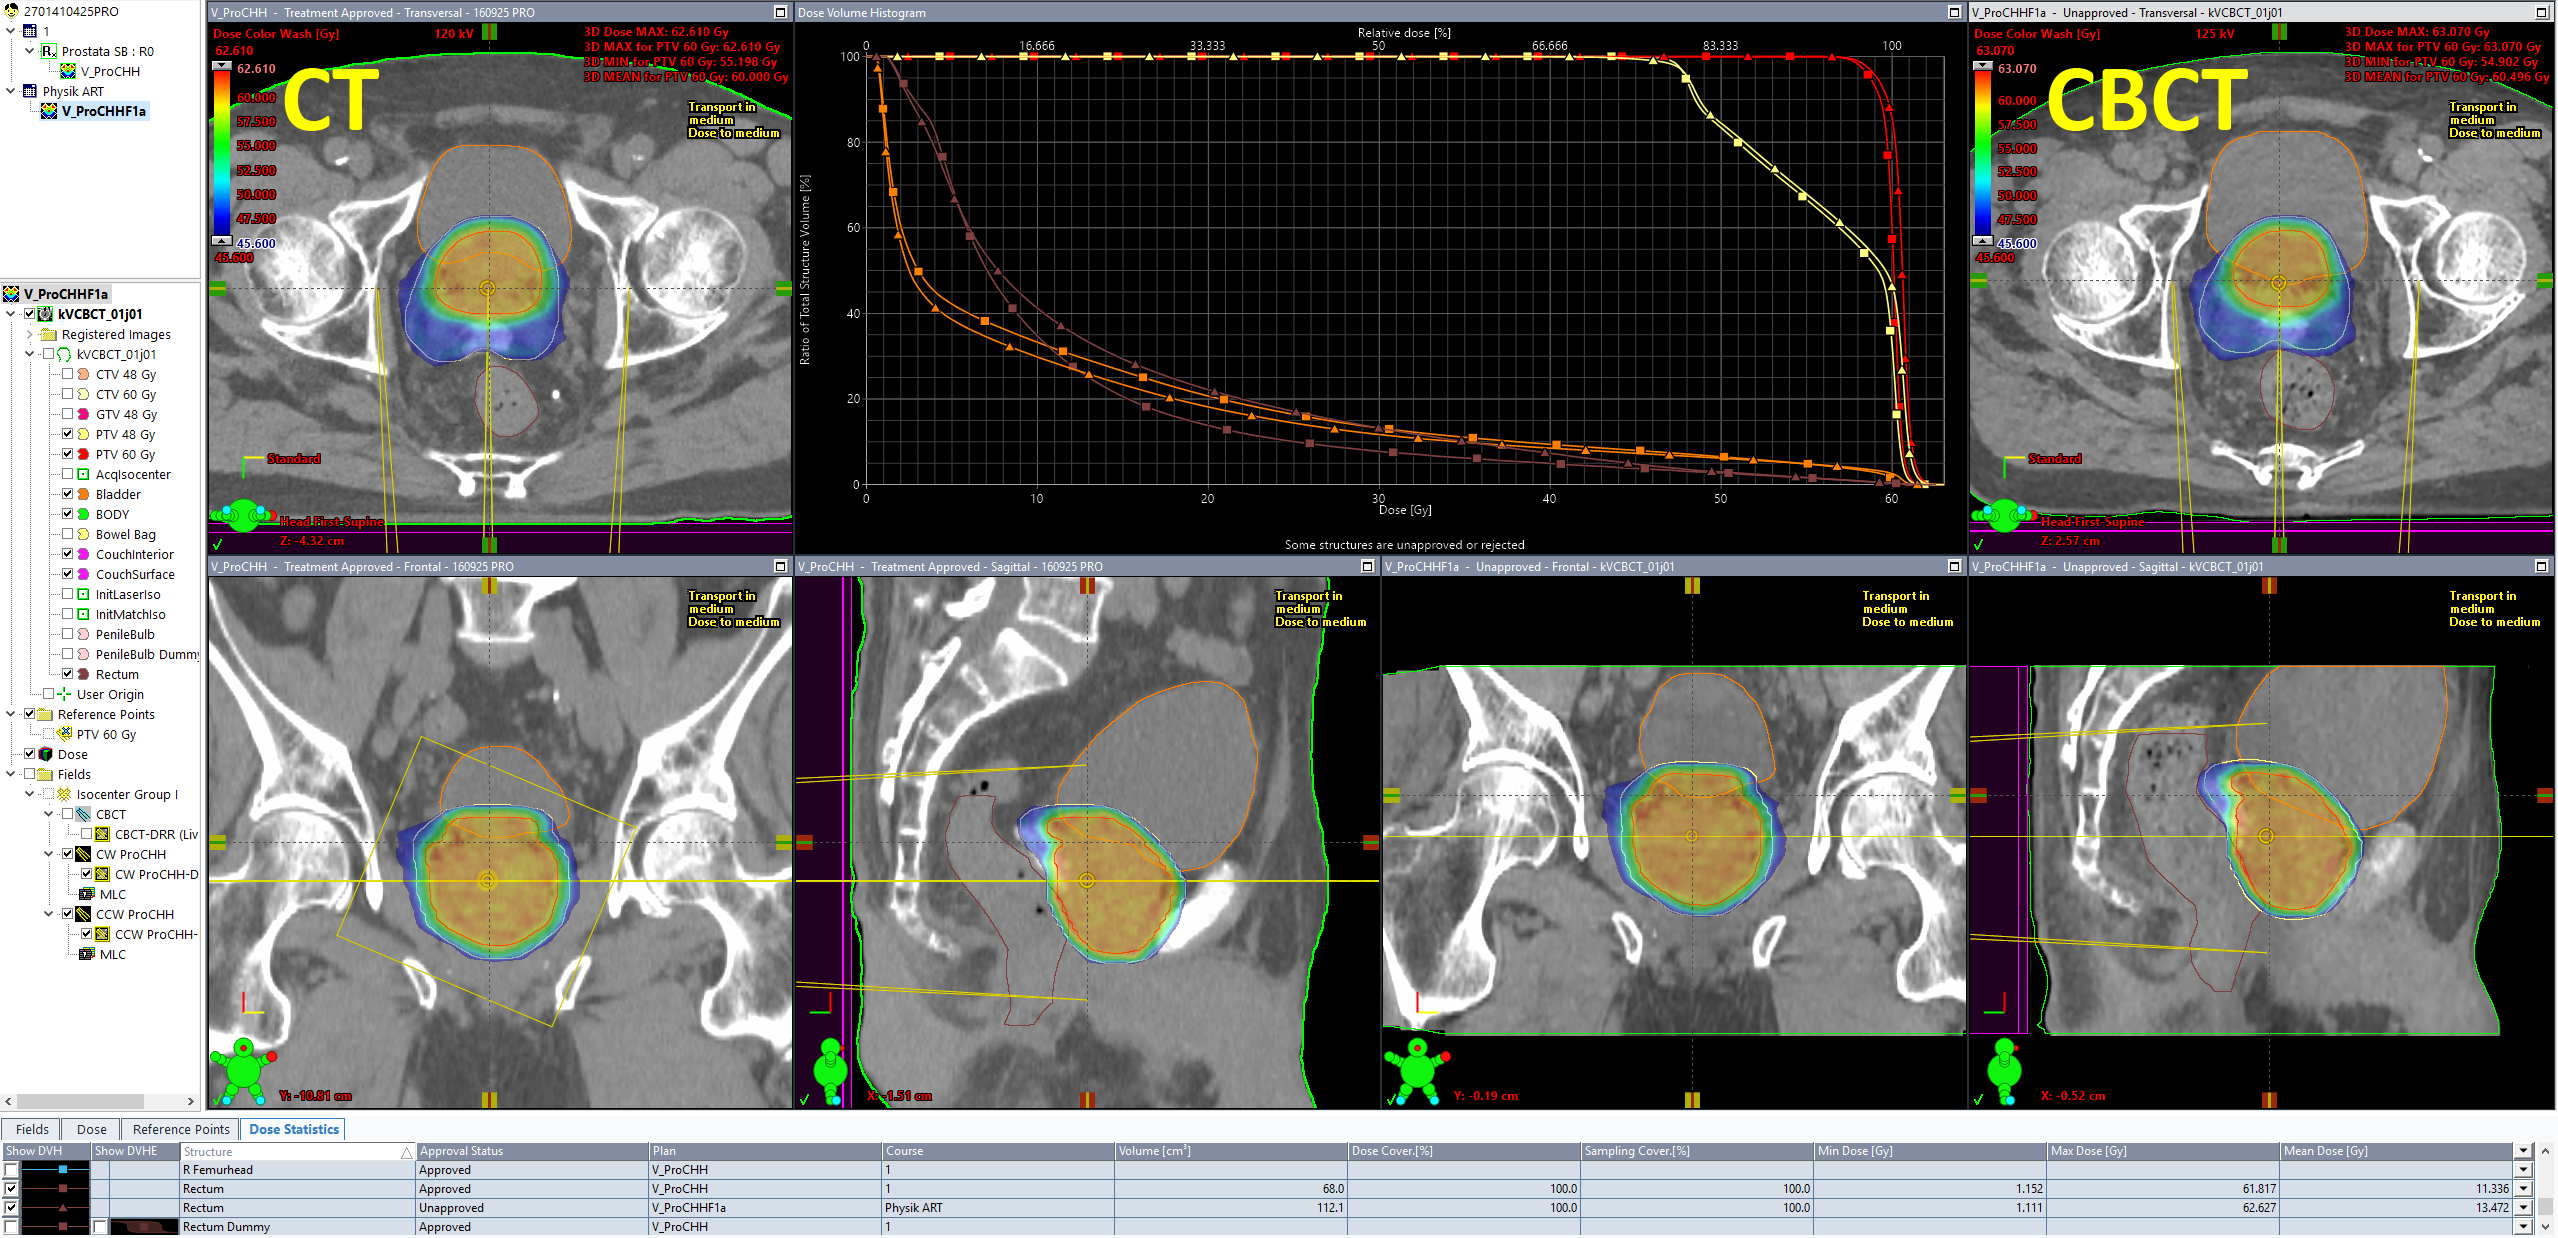

It is good to see that target doses (DVH curves in red and yellow) are very close: in today's session (triangles) the mean PTV60 dose was 60.496 Gy (+0.8%), whereas the original plan (squares) had been normalized to target mean (60.000 Gy).

During contouring of the CBCT, we had already seen that the rectum - in spite of the SpaceOAR hydrogel - was a little closer to the high dose region than in the planning CT. This is confirmed by its mean dose, which is a little higher:

All dose values are for 20 sessions. A mean dose of 13.472 Gy instead of the 11.336 Gy in the original plan means that if the anatomic situation in all 20 sessions would be as it was today, rectum mean dose would be 2.1 Gy higher than planned. We all know that this is unlikely. This is exactly what a good ART management system should provide: keeping track of all the doses for (example) 20 individual plans with 20 individual sets of DVHs.